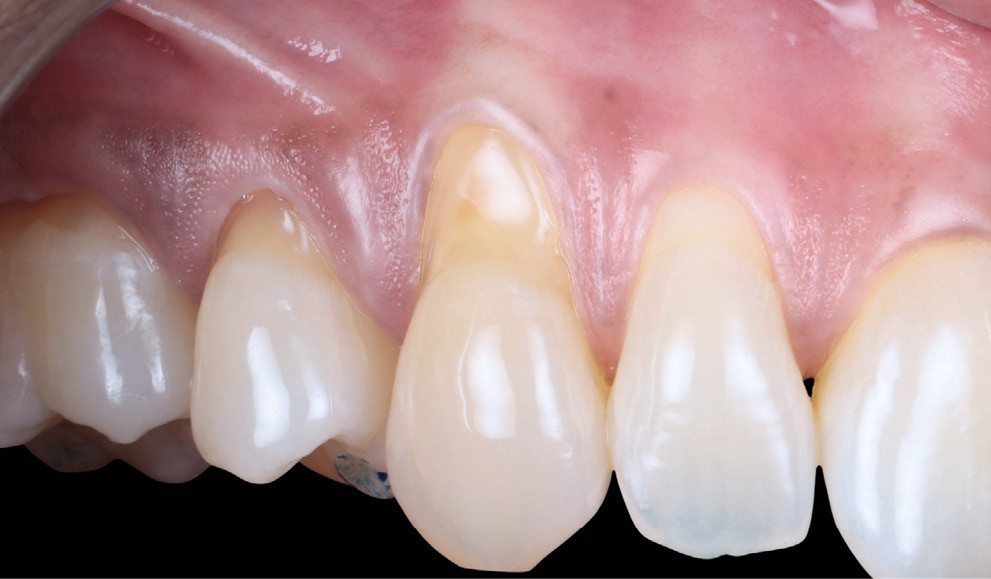

Le choix de la technique est guidé par un arbre décisionnel [4] prenant en compte le nombre de récessions, la quantité de tissu kératinisé et plusieurs points clés. Ici, ce sont les papilles qui vont guider notre décision :

- secteur 2 : papille distale de 23 dodues et malposition de 24 (fig. 3) ➠ CAF (lambeau déplacé coronairement).